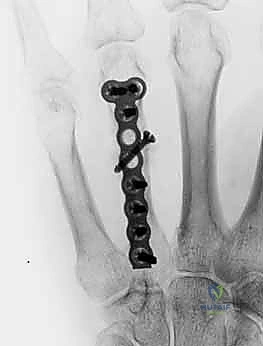

2. التثبيت الداخلي بالصفائح والبراغي المصغرة (Mini-Plates & Screws)

في حالات الكسور المتفتتة (Comminuted) أو الكسور الحلزونية الطويلة التي تميل للانزلاق، يلجأ الدكتور هطيف إلى التثبيت الداخلي المفتوح (ORIF). يتم استخدام صفائح معدنية دقيقة جداً (مصنوعة من التيتانيوم) تتناسب مع حجم عظام اليد.

* الميزة: تثبيت صلب وقوي جداً (Rigid Fixation)، مما يسمح للمريض ببدء العلاج الطبيعي وتحريك أصابعه في اليوم التالي للعملية، وهو أمر بالغ الأهمية لمنع تيبس الأوتار.

خطوات التثبيت الجراحي - توثيق بصري (Intraoperative Imaging)

يحرص الدكتور هطيف على توثيق خطوات العمل الجراحي لضمان أعلى مستويات الدقة. نستعرض هنا مجموعة من الصور من داخل غرفة العمليات توضح مدى تعقيد ودقة هذه الجراحات:

معرض الصور الشعاعية: تقييم النتائج الجراحية (Post-Op X-rays)

النجاح الحقيقي يُقاس بالاستعادة المثالية للشكل التشريحي للعظم. توضح هذه الصور الشعاعية بعد الجراحة الدقة المتناهية في إعادة محاذاة العظام وتثبيتها.

التثبيت المحكم يسمح بالشفاء العظمي الأولي (Primary Bone Healing) دون تكوين كتلة عظمية كبيرة (Callus) قد تعيق حركة الأوتار المنزلقة فوقها.

تعرض شاب رياضي لكسر متبدل ومعقد في العظمة المشطية الثانية والثالثة إثر سقوط عنيف أثناء تدريب رياضي. كان التخوف الأكبر هو فقدان قوة القبضة التي يعتمد عليها في مسيرته. أجرى أ.د. محمد هطيف جراحة تثبيت داخلي باستخدام صفائح التيتانيوم المصغرة. بفضل التثبيت القوي، بدأ المريض العلاج الطبيعي في اليوم الثالث، وعاد لممارسة نشاطه الرياضي الكامل بعد 8 أسابيع فقط.